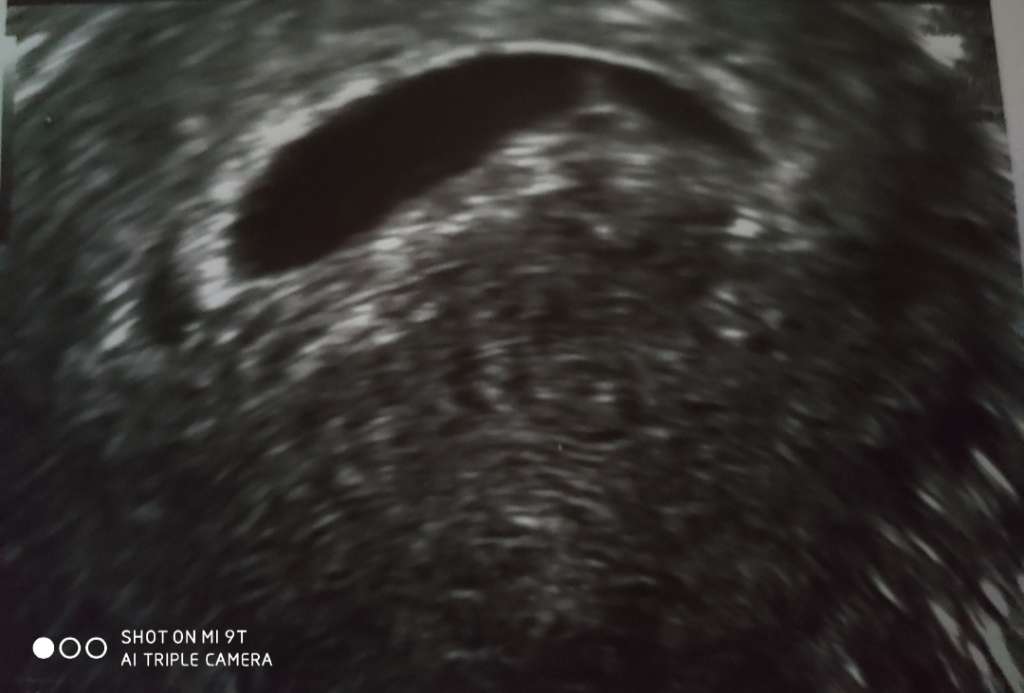

Uff jaka ulga, jestem po wizycie. Człowieczek ma 3mm, serduszko bije, termin z usg 19.09 🥰.

• 5f1af0ec-0006-4d34-86f7-784e2f8b4522.jpg

5f1af0ec-0006-4d34-86f7-784e2f8b4522.jpg

33 KB · Wyświetleń: 117